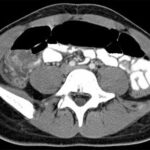

Adipose Tissue Classification and Quantification from MR and CT Imaging

The study of adipose tissue is motivated by the negative consequences of obesity. Countless studies have reported that obesity is associated with an increased risk of heart disease, diabetes and other gastrointestinal diseases, and certain cancers. A search of the term “fat” in the Analyze Publications Database returns over 150 fat-related research articles in which…